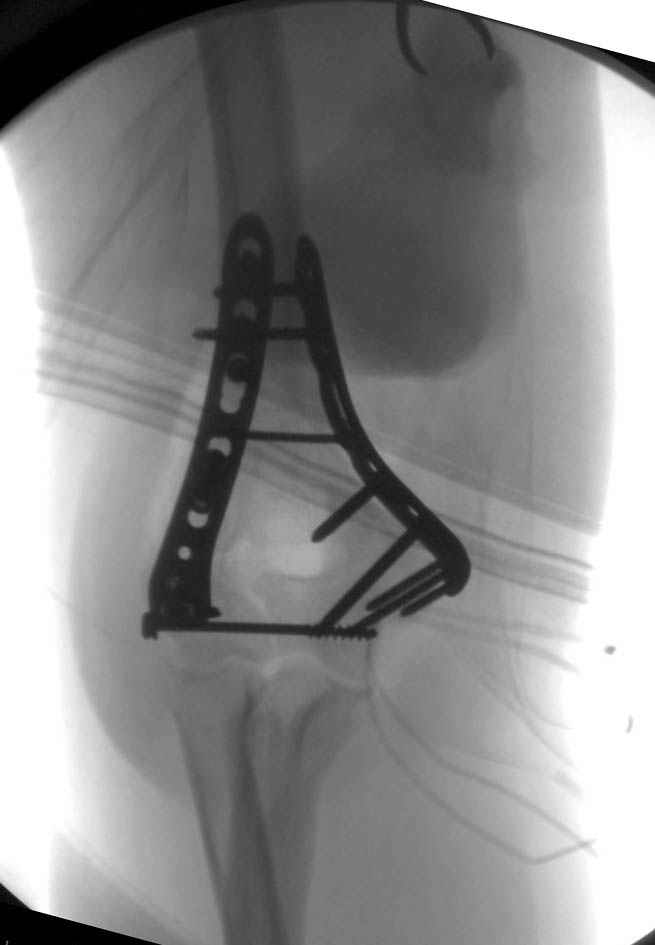

Djoldas Kuldjanov, M.D. 09 Сентябрь 2005, 20:07

Примерный случай, только перелом был открытый, в задне-медиальной стороне рана около 2 см по характеру "изнутри кнаружи", неврологический статус со слабостью сгибания мизинца, также слабая абдукция и аддукция указательного пальца и сгибания в кисти.

Больному сделали обработку и наложили временный аппарат внешной фиксации плечо-предплечье.

На шестой день сделали открытую репозицию чрезлоктевым доступом двумя locking plate, локтевой нерв был ушибленным, после операции положительная динамика в Flexor Carpi Ulnaris. Фиксацию локтевого отростка произвели tension band technique с дополнительным шурупом.

Этапы операции на снимках....